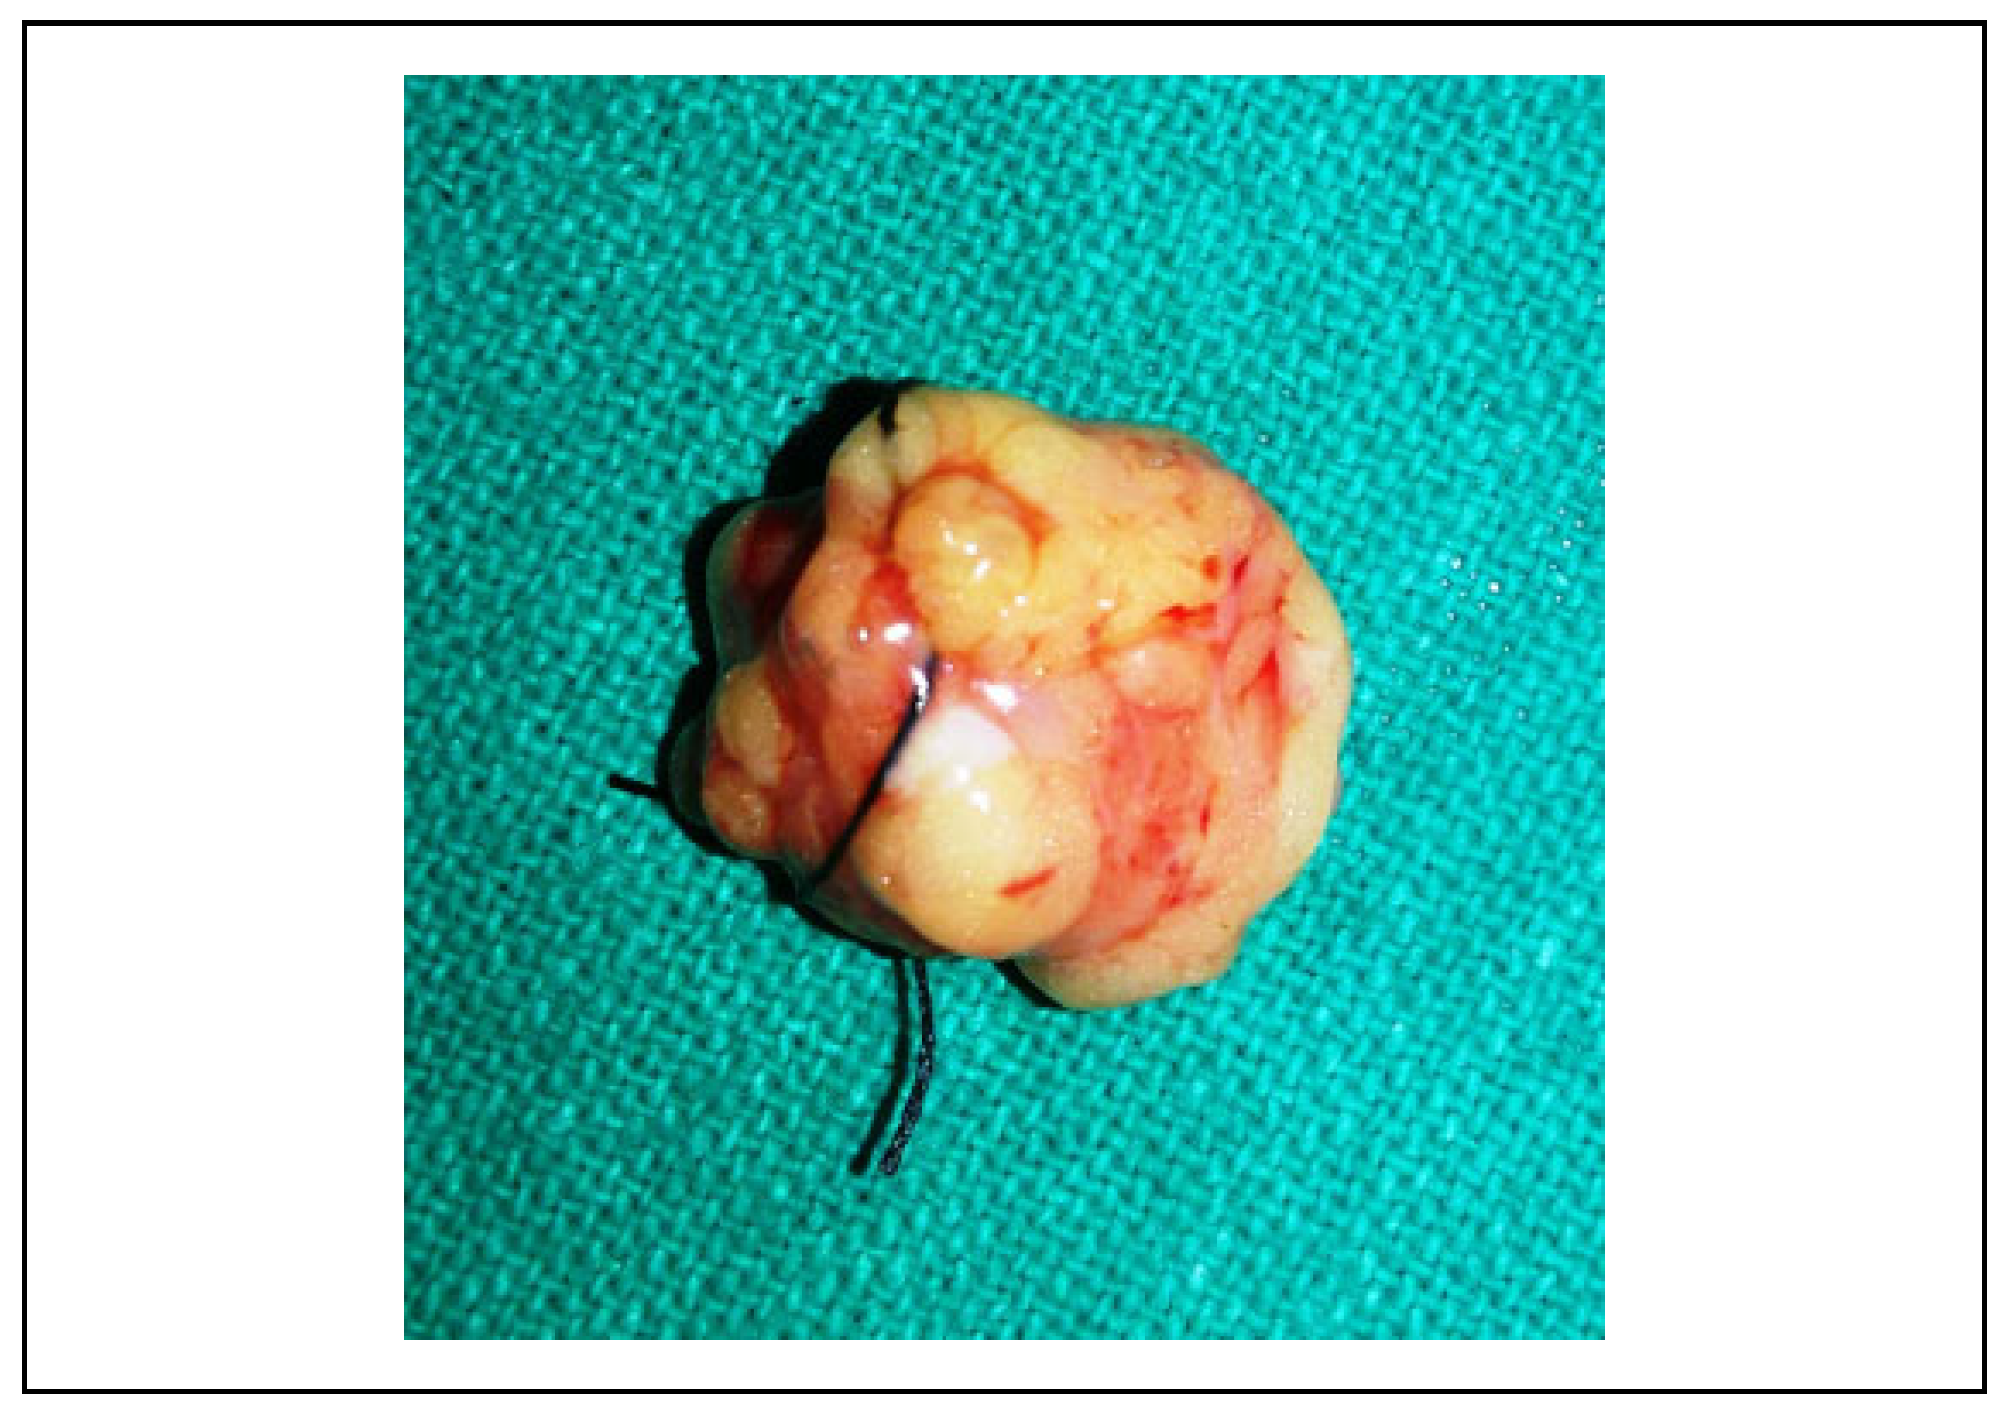

A Clinical and Radiological Investigation of the Use of Dermal Fat Graft as an Interpositional Material in Temporomandibular Joint Ankylosis Surgery

Rahman, S.A.; Rahman, T.; Hashmi, G.S.; Ahmed, S.S.; Ansari, M.K.; Sami, A. A Clinical and Radiological Investigation of the Use of Dermal Fat Graft as an Interpositional Material in Temporomandibular Joint Ankylosis Surgery. Craniomaxillofac. Trauma Reconstr. 2020, 13, 53-58. https://doi.org/10.1177/1943387520903876